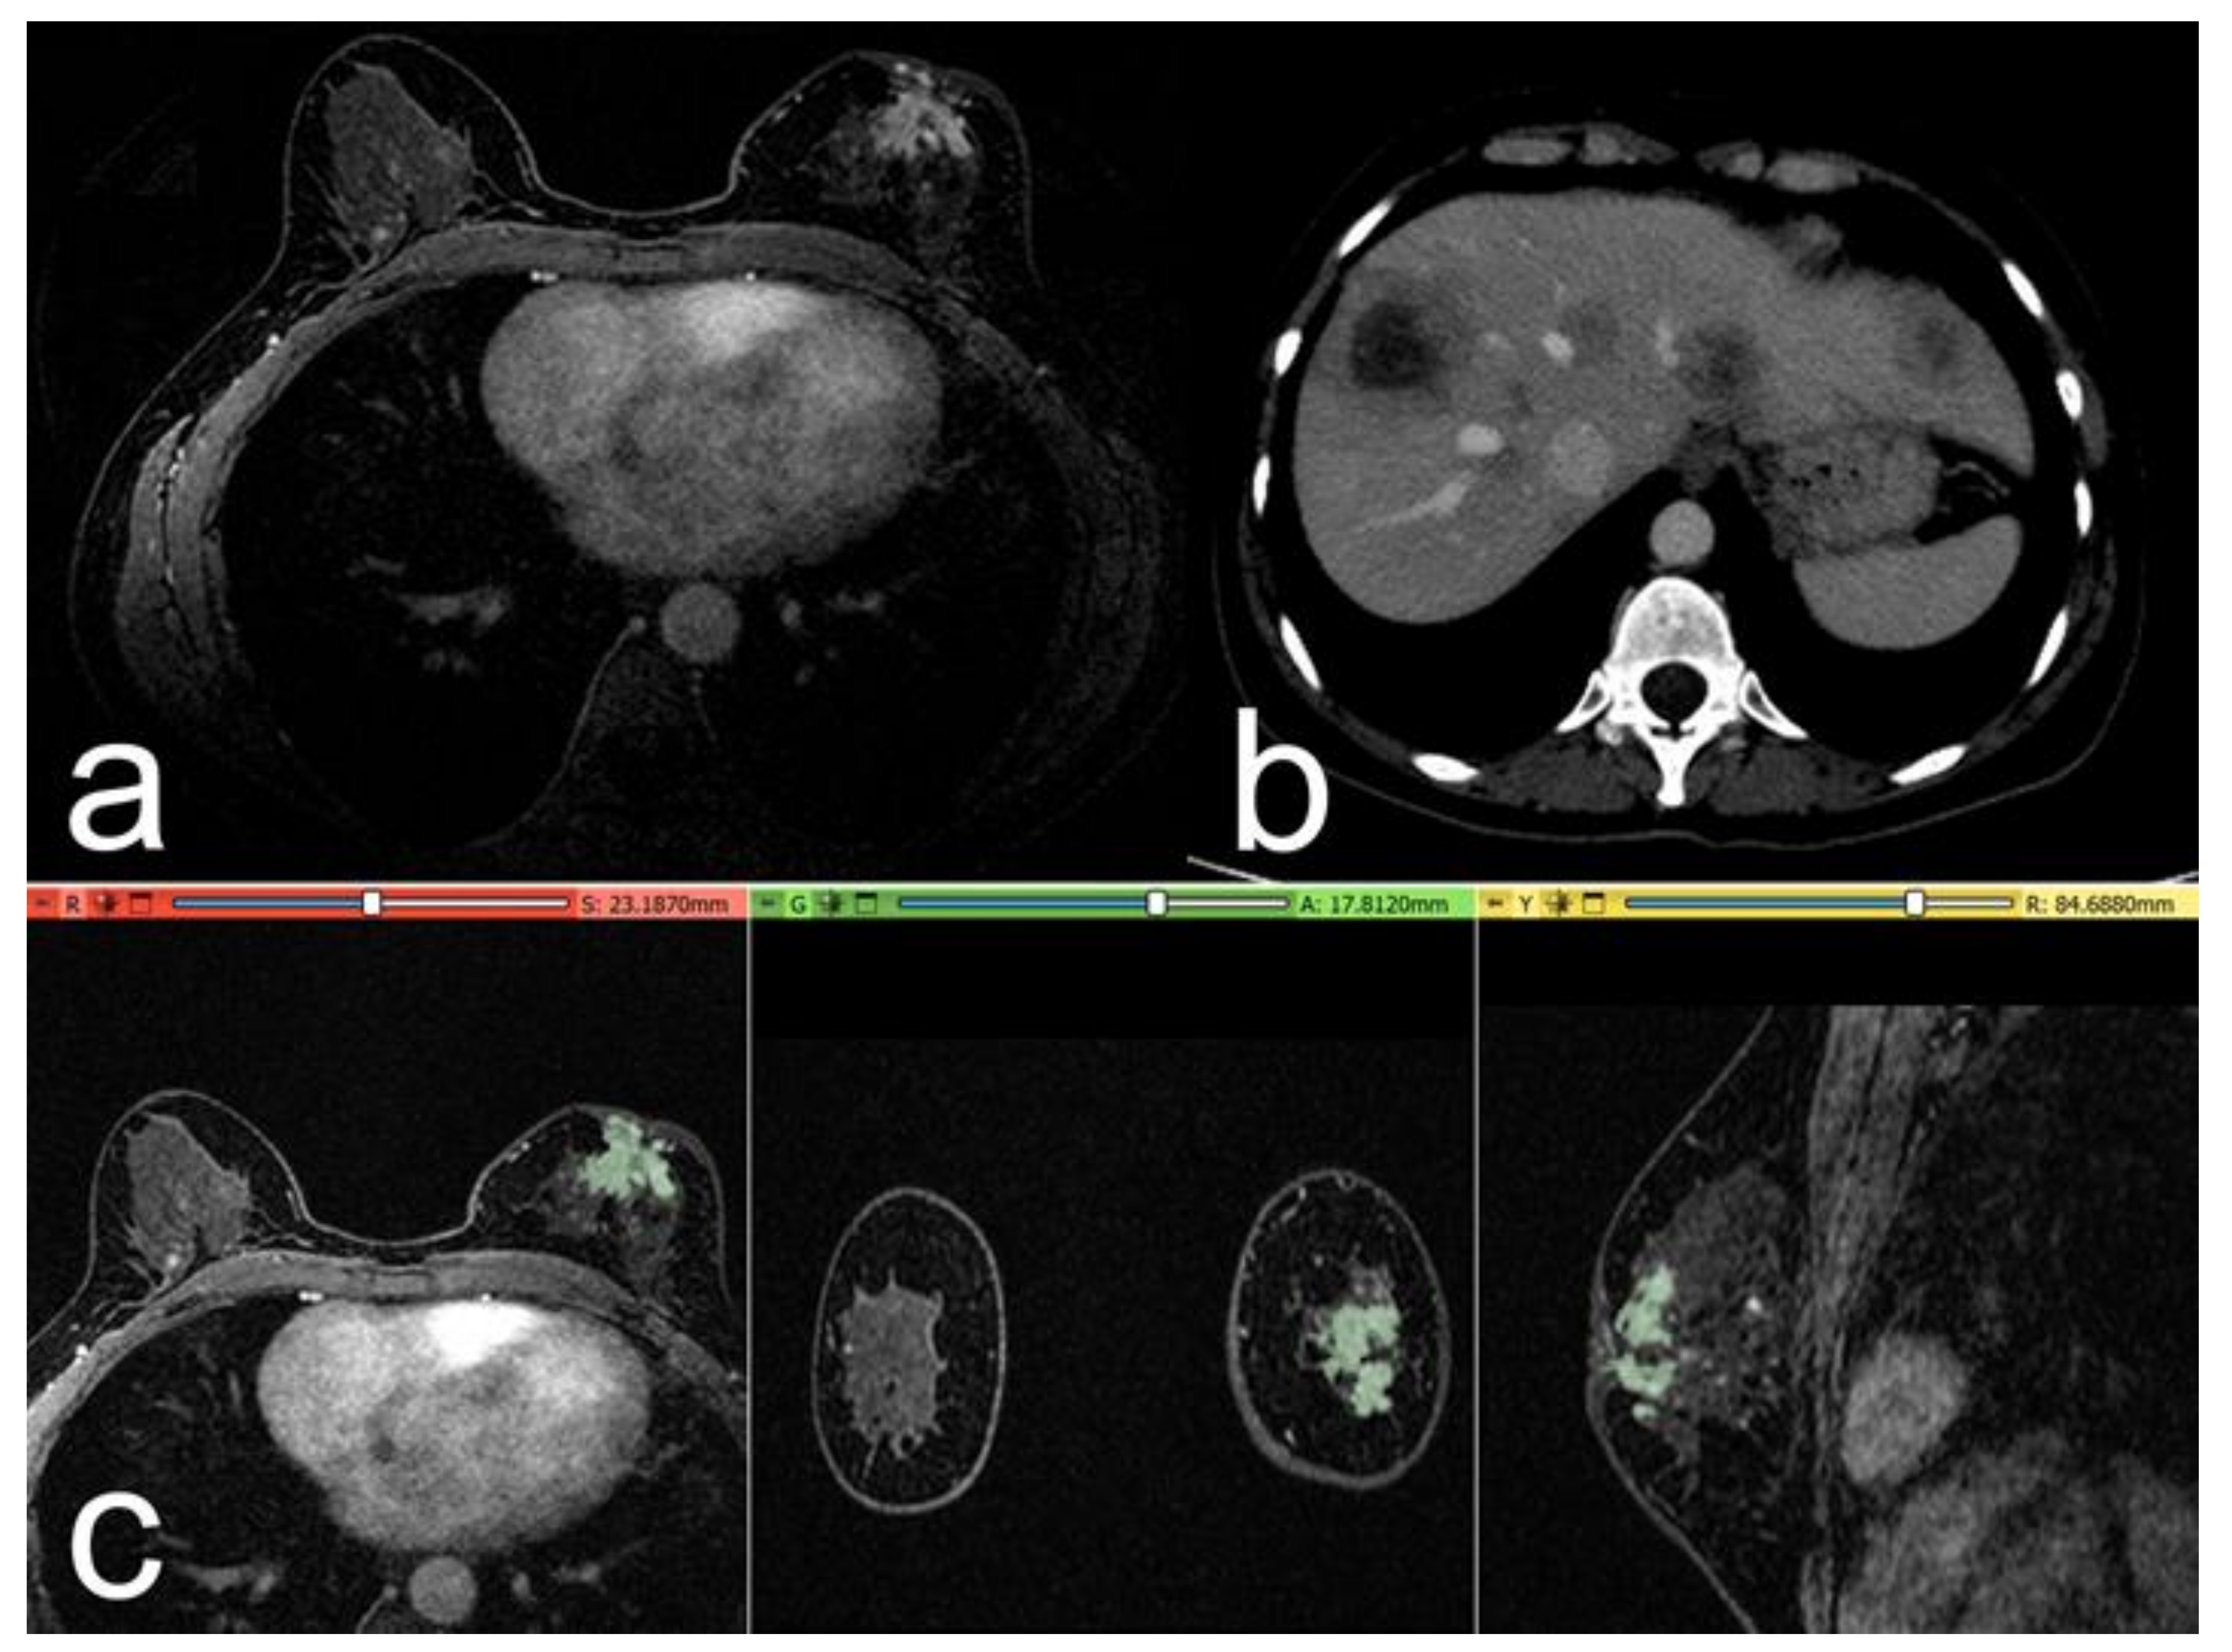

Simple Summary

2. Materials and Methods

2.4. Segmentation and Pre-Processing

2.5. Volumes Extraction